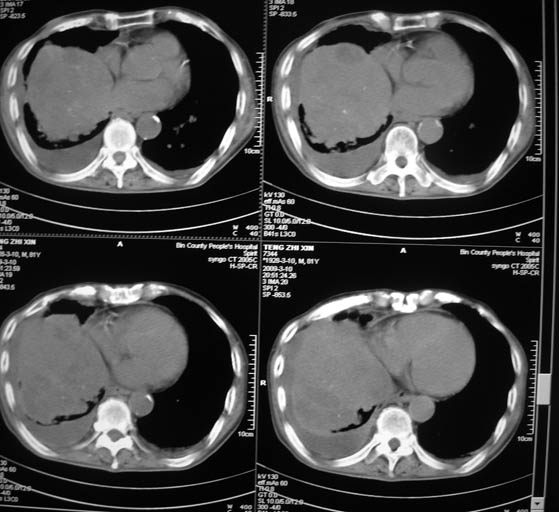

标题: CT18642:男,81岁,发热待查。

男,81岁,发热待查,右侧是占位还是膈疝?

右中央型肺癌并双肺及胸膜、肝脏转移

支持,肿块巨大,内有钙化\\坏死,肺肉瘤要考虑

右中心型肺癌并双肺及胸膜、肝脏转移!